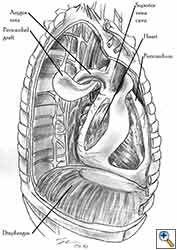

Medium and large-sized (Figures 1a, 1b) defects generally result after pneumonectomy for advanced central lung tumours which invade the pericardium (T3 invading pericardium), thus requiring reconstruction (Figure 1c). To achieve a curative resection, negative pericardial resection margins must be obtained and checked microscopically. More invasive tumours (T4 invading cardiac structures) require partial atrial resection and pericardiectomy associated with pneumonectomy.

|

| Figure 1c: Intraoperative aspect of pericardioplasty with Marlex mesh after right completion pneumonectomy with partial pericardiectomy. |

Video 1 depicts a pericardial reconstruction with Marlex after a right completion pneumonectomy with pericardiectomy for lung adenocarcinoma (see also Figure 1). The technique of pericardial reconstruction after the resection of invasive mediastinal tumours is illustrated in Figures 8a-c). Video 2 depicts a pericardial reconstruction with Mersilene mesh after the resection of a malignant thymoma invading the anterior pericardium (see also Figure 4b). The technique of right pericardial reconstruction after extrapleural pneumonectomy is illustrated in Figures 9a and 9b). Video 3 depicts a pericardial reconstruction using Gore-Tex Dual Mesh after a left extrapleural pneumonectomy (see also Figure 3). Care must be taken to prevent constriction (Figure 10).